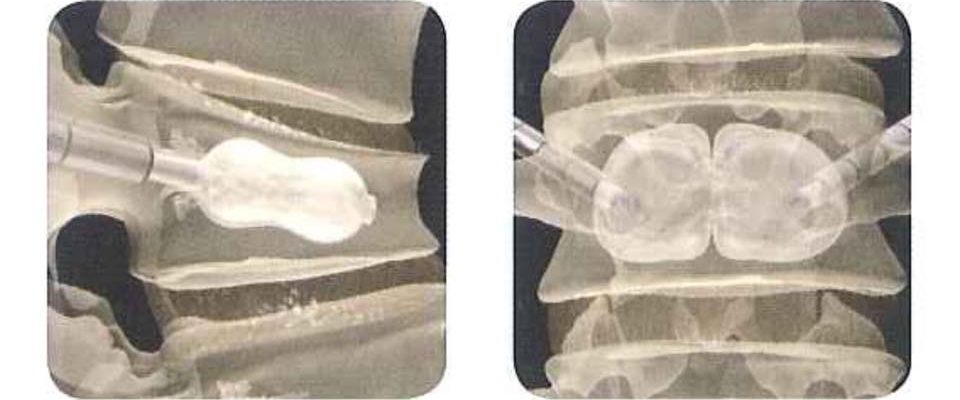

腰椎體後凸成形術和腰脊椎體成形術